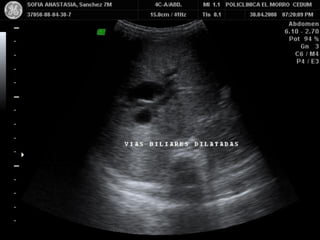

VIAS BILIARES

INTRAHEATICAS Y EXTRAHEPATICAS

DILATACION BILIAR

INTRAHEPATICA

Dilatación biliar en cornamenta

de ciervo